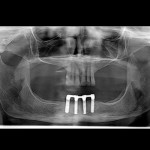

Este é um caso mais simples de se fazer e com um valor (custo-benefício) bastante cómodo.São somente 4 implantes na arcada inferior suportando uma barra sobre a qual será transferido em parte o esforço mastigatório. É confeccionada em RESINA como uma prótese total convencional.